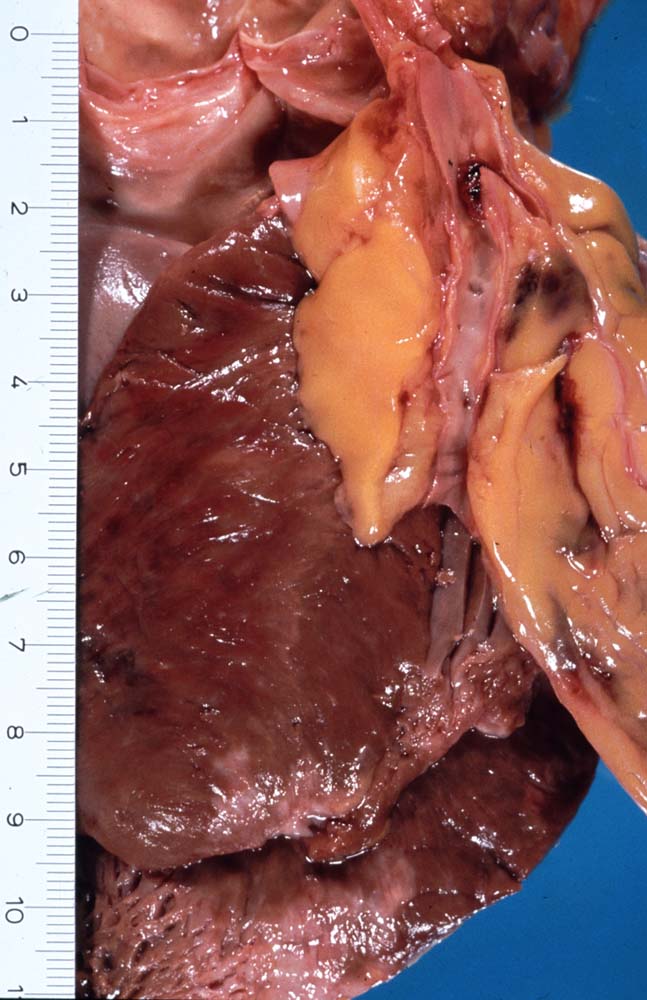

PathoPic – image database / PathoPic ID 8854 - Koronarthrombose

Koronarthrombose

An der Bifurkation des RIVA/Ramus diagonalis ist das Lumen des RIVA thrombosiert. Auf der Schnittfläche der Vorderwand ist eine Infarktnarbe und eine fleckige Verfärbung des Myokards (akuter Myokardinfarkt) erkennbar.